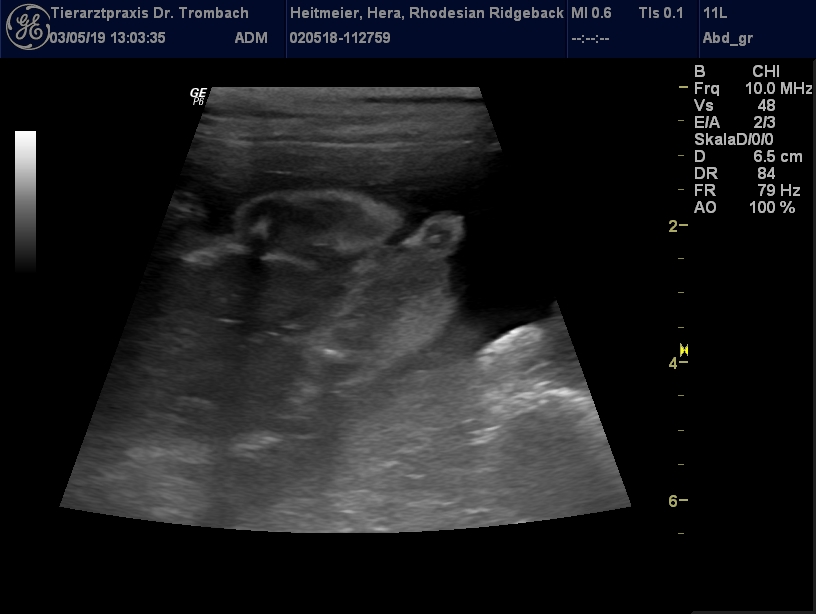

waren bei unserer Ärztin und haben nochmals geschallt...

8 kleine Früchtchen konnte Sie erkennen!